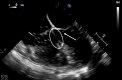

Tetralogy of Fallot (TOF) is a heterogeneous congenital heart disease that is occasionally diagnosed during adulthood. However, although they are often asymptomatic, adult patients with uncorrected TOF often have a poor prognosis. Poor outcomes indicate the importance of the identification and management of these patients, especially in the context of intercurrent disease or noncardiac surgery. We describe a case of clinically silent TOF in a 51-year-old woman. TOF was unmasked during a major noncardiac surgery for a polytrauma and successfully treated with the cooperation of a multidisciplinary team. (Level of Difficulty: Advanced.).